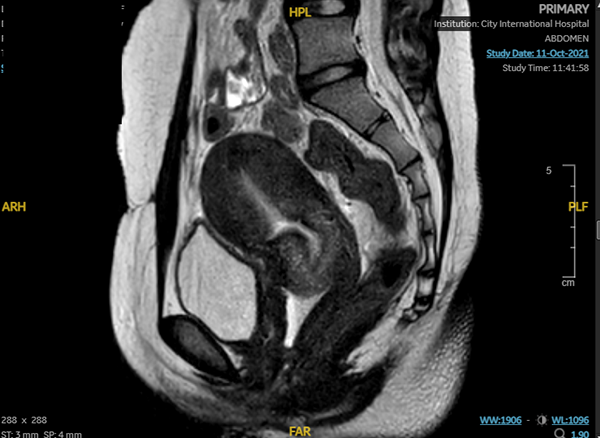

Sau phẫu thuật 2 tuần: tử cung – âm đạo không còn ứ máu